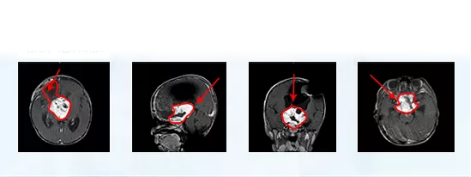

國內(nèi)一次手術(shù)后

視神經(jīng)膠質(zhì)瘤手術(shù)圖片

德國巴教授INI手術(shù)結(jié)果

更新診斷“視神經(jīng)膠質(zhì)瘤”,

腫瘤全切,未殘留長期神經(jīng)功能障礙,

術(shù)后兩周出院,視力明顯好轉(zhuǎn),

可自行站立、短距離行走。